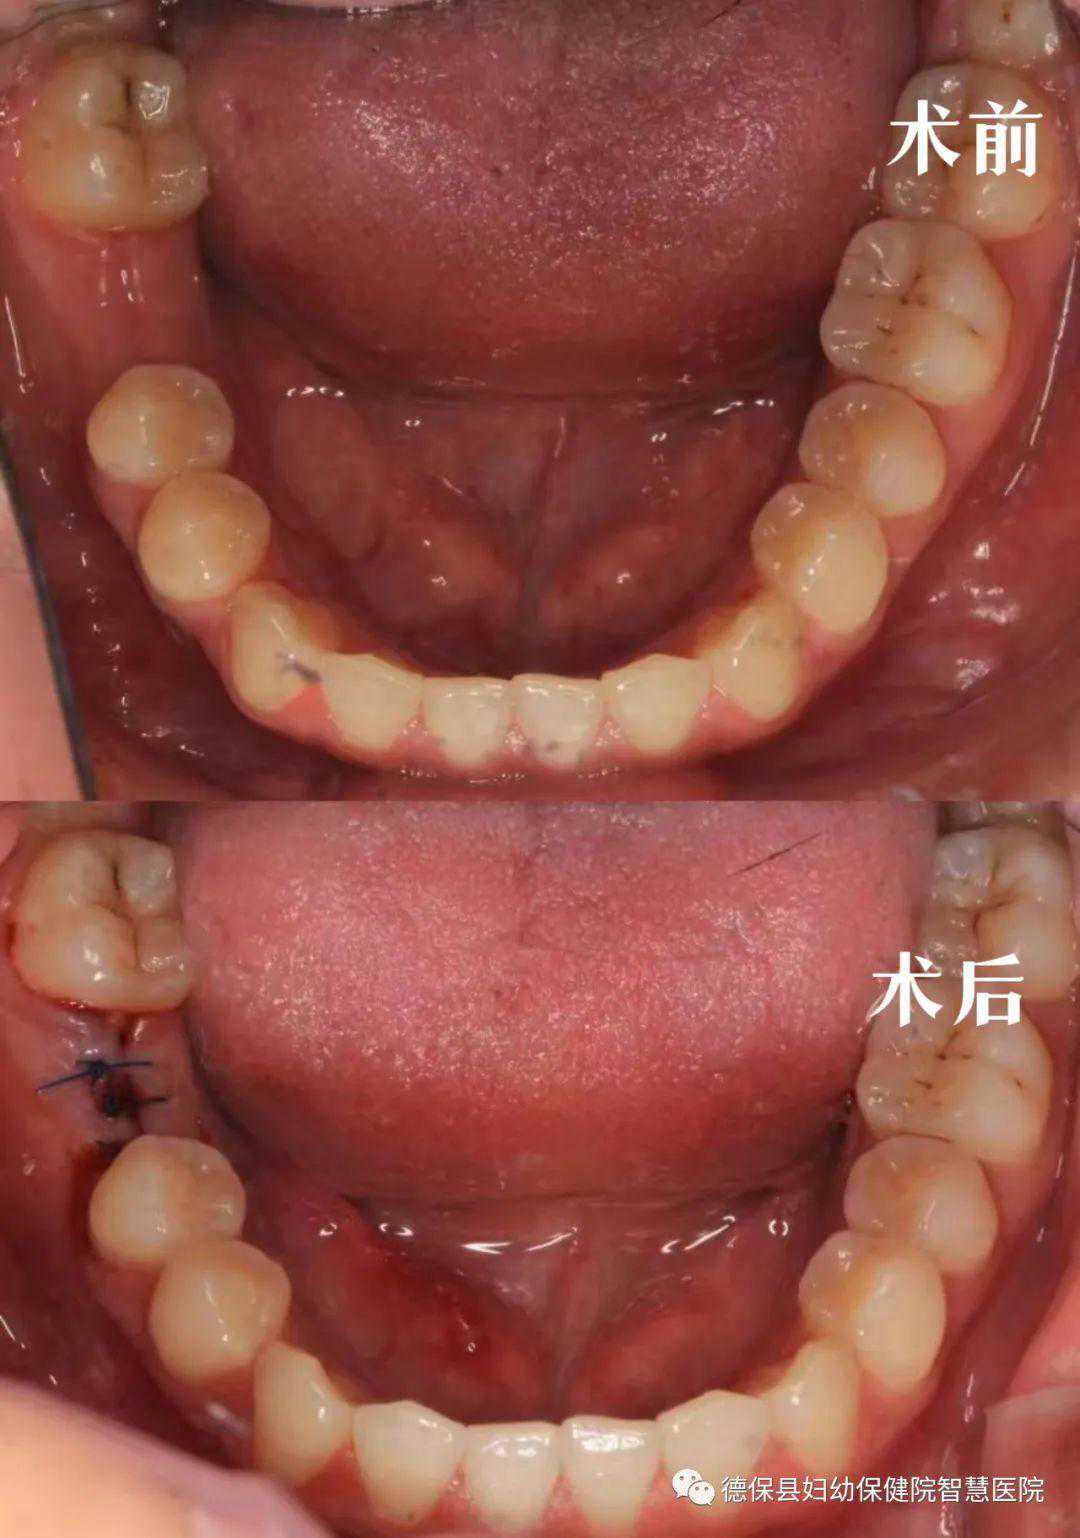

(口内照)